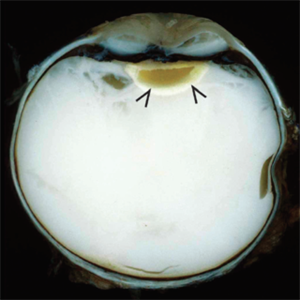

Nongranulomatous uveitis is a group of diseases often related to systemic autoimmune diseases such as arthritis. In this enucleation specimen, the choroid is diffusely thickened (arrow) and a choroidal detachment is present (*). The retina is opaque and the lens is cataractous.